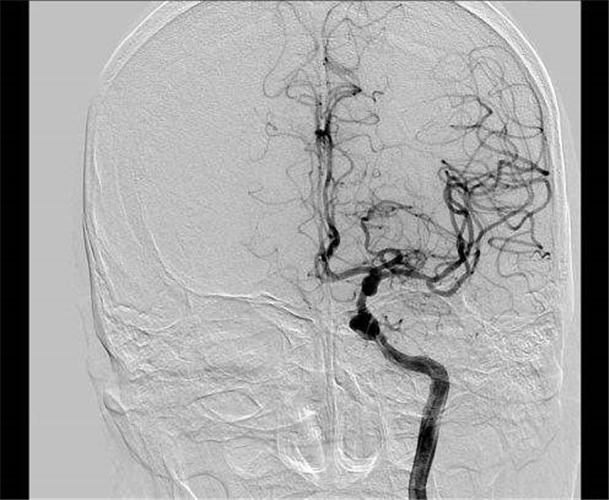

左頸內動脈狹窄導致腦供血不足

腦供血不足血管造影